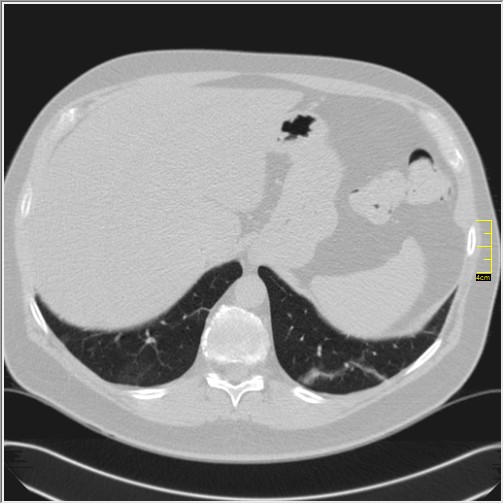

Četiri dana kasnije. Isti pacijent dolazi sa istim pulmologom. Situacija je sada sasvim drugačija. Temperatura 39.5C.Saturacija 92. Laboratorija daleko gora. Uradim CT pluća. Ovo je izašlo

Severity score 15/25. Pacijent je upućen na bolničko lečenje.

Ono što zbunjuje a to se ponavlja zadnjih 10 dana, je da fibroza nastupa u progresivnoj fazi, znači na početku bolesti. Toga nije bilo do sada. Sledećih dana ću o tome.

Ovo je samo 4 dana. Od zdravlja do teške bolesti. Pacijent je 45 godina starosti, očigledno nije povećane težine, kaže za sebe da je bio sportista. U anamnezi nije naveo nikakve bitne bolesti.